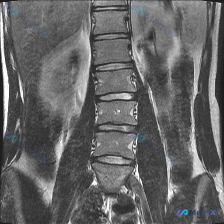

整理到一份有意思的影像读片资料:用户提问直接指向「观察到脊柱侧弯(Scoliosis)」,但附上的腰椎MRI T1加权像(冠状位)的专业读片结果,好像和这个预设有点不一样。

先放影像核心表现:

- 观察节段:L1-L5

- 椎体:形态完整,皮质连续,无楔形变/塌陷/破坏

- 骨髓:弥漫均匀中高信号(符合正常成人脂肪骨髓)

- 椎间隙/椎间盘:高度大致正常,T1中等信号,无明显侧方突出

- 脊柱力线:整体居中,未见明显侧弯畸形

- 双侧椎弓根、横突、腰大肌:基本对称

📋答案:1. 首要诊断:正常解剖结构(阴性发现);2. 核心判定:基于现有腰椎MRI冠状位T1WI,排除结构性脊柱侧弯